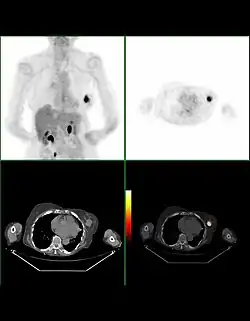

Bilan d'extension

La recherche de métastases est fondamentale dans la stratégie du traitement du cancer du sein. Mais, malgré les nombreuses études réalisées ou la connaissance approfondie de certaines explorations, il n'existe actuellement aucune stratégie validée de recherche systématique de métastase dans le cancer du sein.

La plupart des recommandations proposent actuellement un bilan d'extension comportant un examen clinique soigneux à la recherche de métastases ganglionnaires, une radiographie thoracique, une échographie hépatique et une scintigraphie osseuse. Pour les tumeurs de très petite taille, ce bilan peut être facultatif.

En revanche, pour les tumeurs évoluées (tumeurs inflammatoires, multifocales, envahissement ganglionnaire important), le risque métastatique initial est élevé et peut justifier un bilan plus poussé comportant une tomodensitométrie corps entier et une IRM mammaire.

La taille de la tumeur, l'existence d'adénopathies métastatiques, l'existence d'une atteinte de la peau ou de la paroi thoracique ou de métastases à distance permettent d'établir une classification clinique des cancers du sein.

Le bilan d’extension permet de classer le cancer selon la classification TNM qui prend en compte la taille de la tumeur, l'absence ou le nombre de ganglions atteints par le cancer et l'existence ou non de métastase. Cette classification est un des critères pour la prise en charge de la maladie.